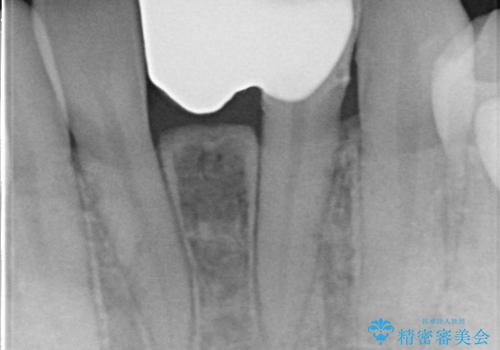

- 下顎前歯の欠損補綴を主訴として治療を行いました。

インプラントやクラウンブリッジは希望されず、接着ブリッジにて治療を行いました。

接着ブリッジは維持をレジン系のセメントのみに依存しているため脱離するリスクは高いです。

適応は下顎前歯の1歯欠損のみとしております。

リテーナー(支台歯)は1歯の方が長期予後が良いとされております。